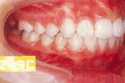

治療前後の比較

受け口

出っ歯

乱抗歯

開咬